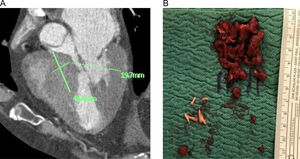

Miectomía septal extendida. Se trata de una miectomía realizada con corte frío según técnica convencional y extendida en sentido craneocaudal hasta las porciones medias del septo o, en casos específicos, hasta la base de implantación de los músculos papilares, procurando mantener un espesor mínimo de seguridad de 10mm para evitar el riesgo de complicación iatrogénica a nivel del septo interventricular. De esta forma, se consigue redirigir parcialmente el flujo hacia la pared anterior2,13. La extensión de la miectomía en términos de longitud y espesor (en mm) se decidió en cada caso en función del estudio de imagen multimodal preoperatorio, sobre todo haciendo referencia a las reconstrucciones 3D y a las mediciones obtenidas en la TC y la RM (fig. 1).

Resección de cuerdas tendinosas aberrantes. Entre las anomalías subvalvulares reportadas en MCH se incluyen cuerdas tendinosas anormales por inserción y/o tamaño. Se trata de conexiones fibrosas, a menudo de espesor/longitud anómalos, dirigidas hacia el septo o la pared libre del ventrículo izquierdo y ancladas a segmentos del velo anterior mitral distintos del borde libre10. La detección y la división con corte frío de estas cuerdas anómalas son de fundamental importancia para liberar el velo anterior y permitir el desplazamiento en sentido posterior de la superficie de coaptación mitral, reduciendo de esta forma el SAM. Las cuerdas anómalas se identificaron en el estudio multimodal preoperatorio y se resecaron por completo intraoperatoriamente tras un examen exhaustivo de las inserciones a nivel del velo anterior y distales (fig. 2).